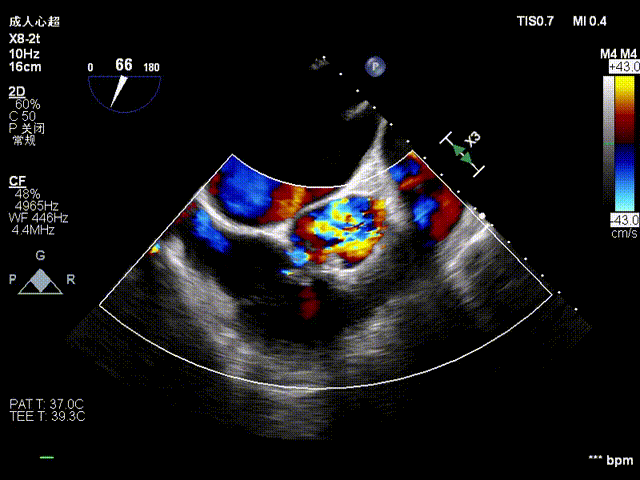

术前超声

术后超声